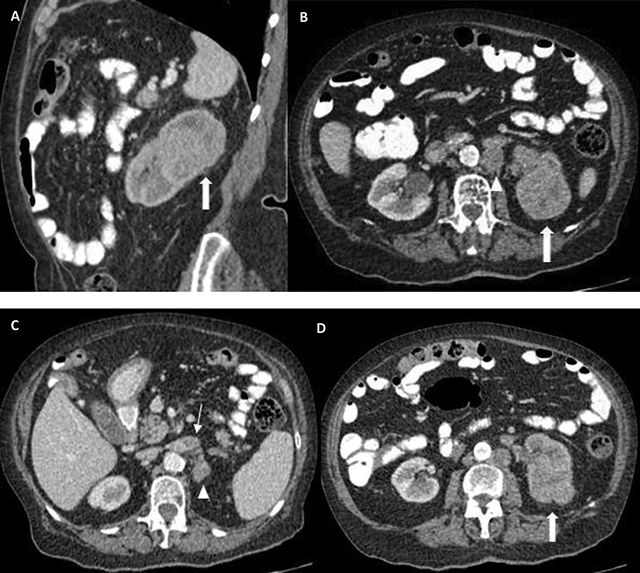

An 80-year-old female patient presented at the emergency department with painless hematuria. Medical history mentioned the presence of uterine leiomyomas. An abdominal CT showed an expansile mass in the upper pole of the left kidney, with extension in sinusal fat, eccentric necrosis, and tumor thrombus in the left renal vein. Large, confluent retroperitoneal lymph nodes were also present (Figure 1). A radical left nephrectomy was performed. The gross specimen showed a multinodular solid mass, with necrosis and invasion in the sinusal fat and the renal vein (Figure 2). The pathology report mentioned a fibrous, encapsulated tumor, with a trabecular-to-tubulopapillary growth pattern and with large tumor cells that had a predominantly eosinophilic cytoplasm. Tumor cells contained a central, round nucleus and a fine-grained-to-vesicular chromatin pattern with an eosinophilic nucleole. Immunohistochemistry showed absence of FH in the tumor epithelium, indicating a FH-deficient RCC, which additionally supported PAX8+/panCK+ (Figure 3).

Figure 1

Expansile mass in the upper portion of the left kidney (thick arrows in A, B, D), with invasion of the sinusal fat tissue (B, D). A delayed nephrogram is apparent secondary to outflow obstruction due to renal vein thrombosis (thin arrow in C). Large, confluent, retroperitoneal lymphadenopathies can be seen (arrowheads in B, C).